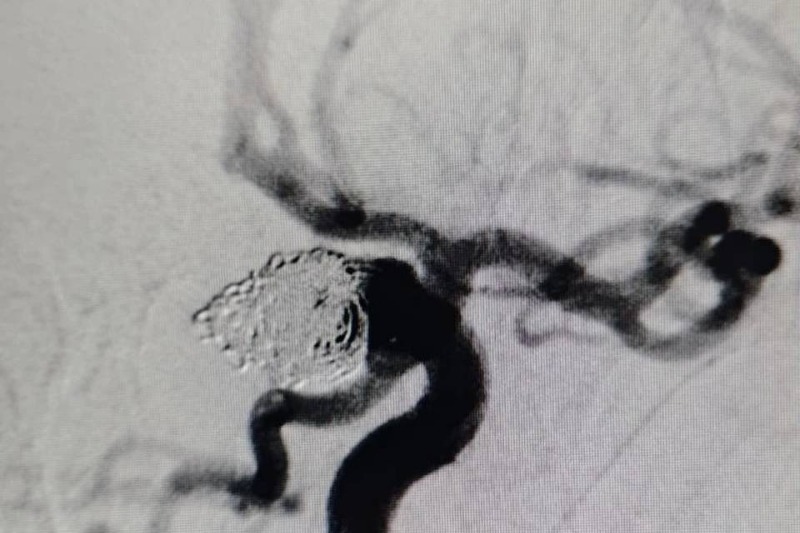

Жизнь 43-летней пациентке с разрывом аневризмы головного мозга спасли эндоваскулярные хирурги, сообщают «Городские вести». Медики провели срочную высокотехнологичную малоинвазивную операцию, которая заключалась в заполнении полости аневризмы микроспиралями. Этот метод блокирует кровоток в аневризме, уменьшая вероятность её разрыва и повторного кровотечения.